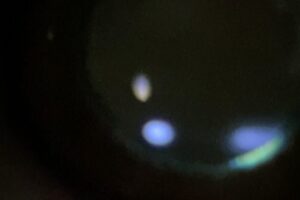

定期的な眼科の健診は視覚の健康を維持するために非常に大切です

眼科における診察の中で、スリットランプは非常に重要な役割を果たしています